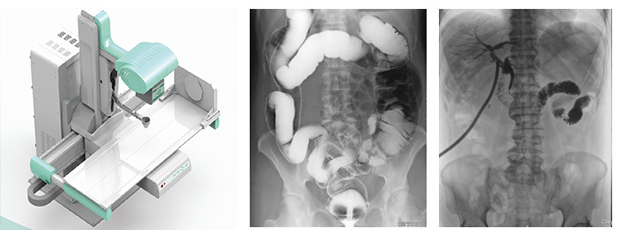

多功能動態(tài)dr由動態(tài)平板探測器、高壓發(fā)生器、球管、運動機架、計算機與圖像處理與傳輸系統(tǒng)組成,與傳統(tǒng)數(shù)字化X線攝影技術(shù)相比,動態(tài)多功能dr攝影能在一個時間單位內(nèi)低劑量高速獲得多幀X線影像,通過圖像算法處理系統(tǒng)后,極速輸出一段連續(xù)動態(tài)影像(運動),實現(xiàn)所見即所得。

多功能動態(tài)dr是集合拍片,透視,造影三種功能為一體的設(shè)備??梢詫μ厥獠≡畈课贿M行高速實時點片,捕獲高清病灶圖,降低了漏診誤診率。特別是對不能配合的患者,也能進行快速高效的檢查,大大減輕了患者的痛苦。